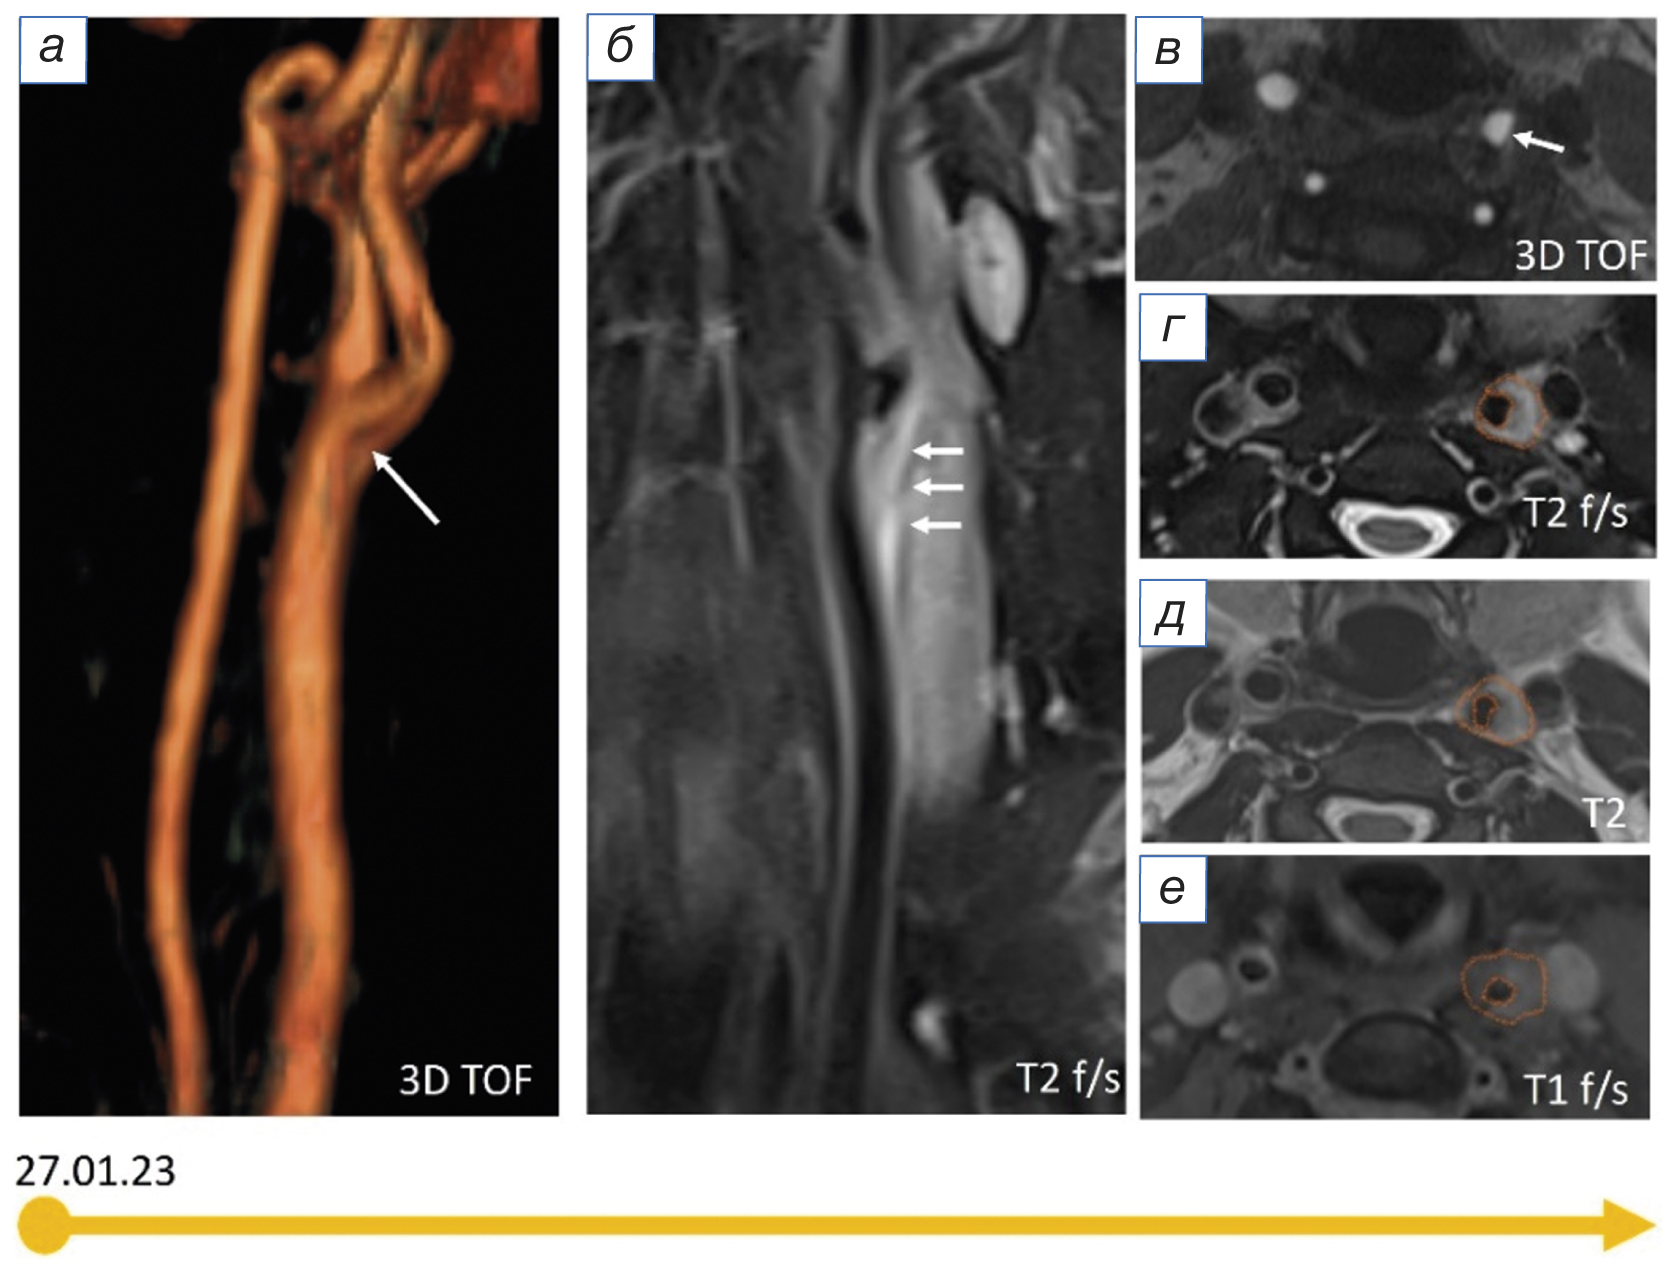

При ретроспективной оценке данных магнитно-резонансной томографии (МРТ) артерий шеи от 27.01.2023 в области бифуркации левой общей сонной артерии визуализировалась периваскулярная, эксцентрично расположенная зона изменённого МР-сигнала без чётких контуров, повышенной интенсивности в Т2 fat-sat (рис. 1 б, г), изоинтенсивная в Т2 (рис. 1 д), изо-/слабогиперинтенсивного сигнала в Т1 fat-sat (рис. 1 е), соответствующая периваскулярному воспалению; наружный контур артерии на этом уровне визуализировался нечётко. При МР-ангиографии (рис. 1 а, в) отмечалось гемодинамически незначимое сужение просвета артерии на этом уровне (рис. 1).

Рис. 1. Результаты магнитно-резонансной томографии шеи пациентки с TIPIC-синдромом в острый период: а, в (3D-TOF-ангиография) — локальное гемодинамически незначимое сужение просвета левой общей сонной артерии (белые стрелки); б, г (Т2 fat-sat), д (Т2), е (Т1 fat-sat) — периваскулярная, эксцентрично расположенная зона изменённого сигнала на уровне бифуркации левой общей сонной артерии (на периваскулярный инфильтрат указывают белые стрелки, красный контур).

Fig. 1. Results of magnetic resonance imaging of the neck of a patient with TIPIC syndrome in the acute period: а, в (3D-TOF-angiography) — local haemodynamically insignificant narrowing of the left common carotid artery lumen (white arrows); б, г (T2 fat-sat), д (T2), е (T1 fat-sat) — perivascular, eccentrically located zone of altered signal at the level of the left common carotid artery bifurcation (perivascular infiltrate is indicated by white arrows, red contour).